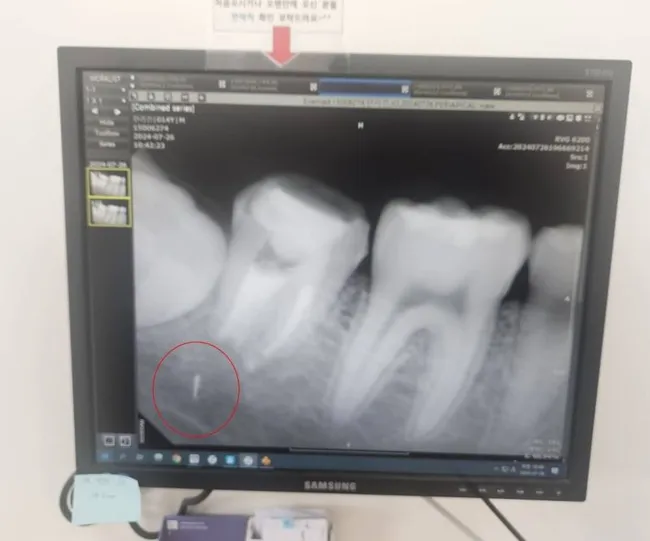

경기 구리시 한 치과의원에서 2024년 4월 중학교 3학년 학생의 턱뼈에 부러진 의료기기 조각이 박히는 사고가 발생했다. 학생은 치료 후 통증과 염증으로 고통받았고, 1개월 뒤 엑스레이 촬영으로 치아 뿌리에 남겨진 의료기기 조각을 발견했다.

학생은 그해 가을 상급병원에서 턱뼈를 갈아내 조각을 제거하려 했으나, 의료진이 신경 손상 위험을 이유로 제거를 중단했다. 현재 의료기기 조각은 턱뼈 안에 그대로 박혀 있으며, 학생은 수업 결손과 일상 활동 제약으로 고통받고 있다. 치과의원 측 보험사는 총 309만원의 합의금을 제시했는데, 이는 병원비 120만원과 위자료 189만원으로 구성됐다.